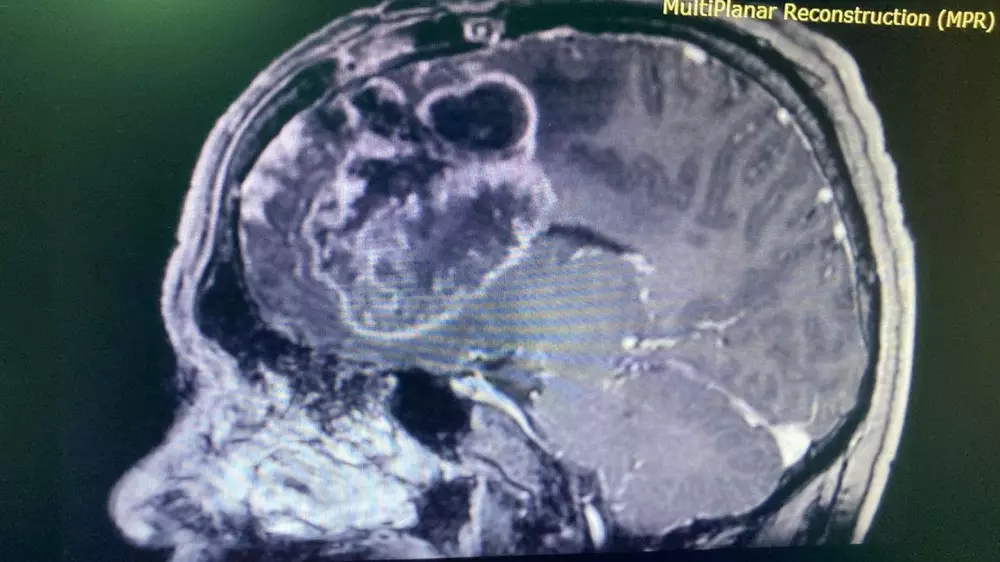

В национальном центре нейрохирургии провели операцию 44-летнему мужчине с глиальной опухолью головного мозга размером 7х7 сантиметров, передает корреспондент Tengrinews.kz.

Мужчина жаловался на головные боли, головокружение, снижение зрения, снижение памяти, слабость в левых конечностях, а также на судорожные приступы. Пациенту был поставлен диагноз "гигантская глиальная опухоль правой лобной доли с прорастанием в мозолистое тело в стадии клинической декомпенсации". Размер опухоли составил семь на семь сантиметров.

Врачи отделения нейрохирургии патологии головного мозга провели шестичасовую операцию по микрохирургическому удалению глиальной опухоли с применением МРТ-трактографии и нейронавигации.

"Прицелившись к опухоли, мы аккуратно обошли двигательные зоны, а также крупные артерии. Также точность удаления опухоли зависела от координат, которые были построены заранее с помощью МРТ-трактографии – это новая методика, показывающая ход и структурные изменения проводящих путей головного мозга (тракты белого вещества), кроме этого, применялась и нейронавигационная система. Благодаря такому технологическому оснащению мы смогли не задеть вышеуказанные структуры и зоны", - рассказал лечащий врач пациента Тлеубергенов Муратбек Абдигалиевич.